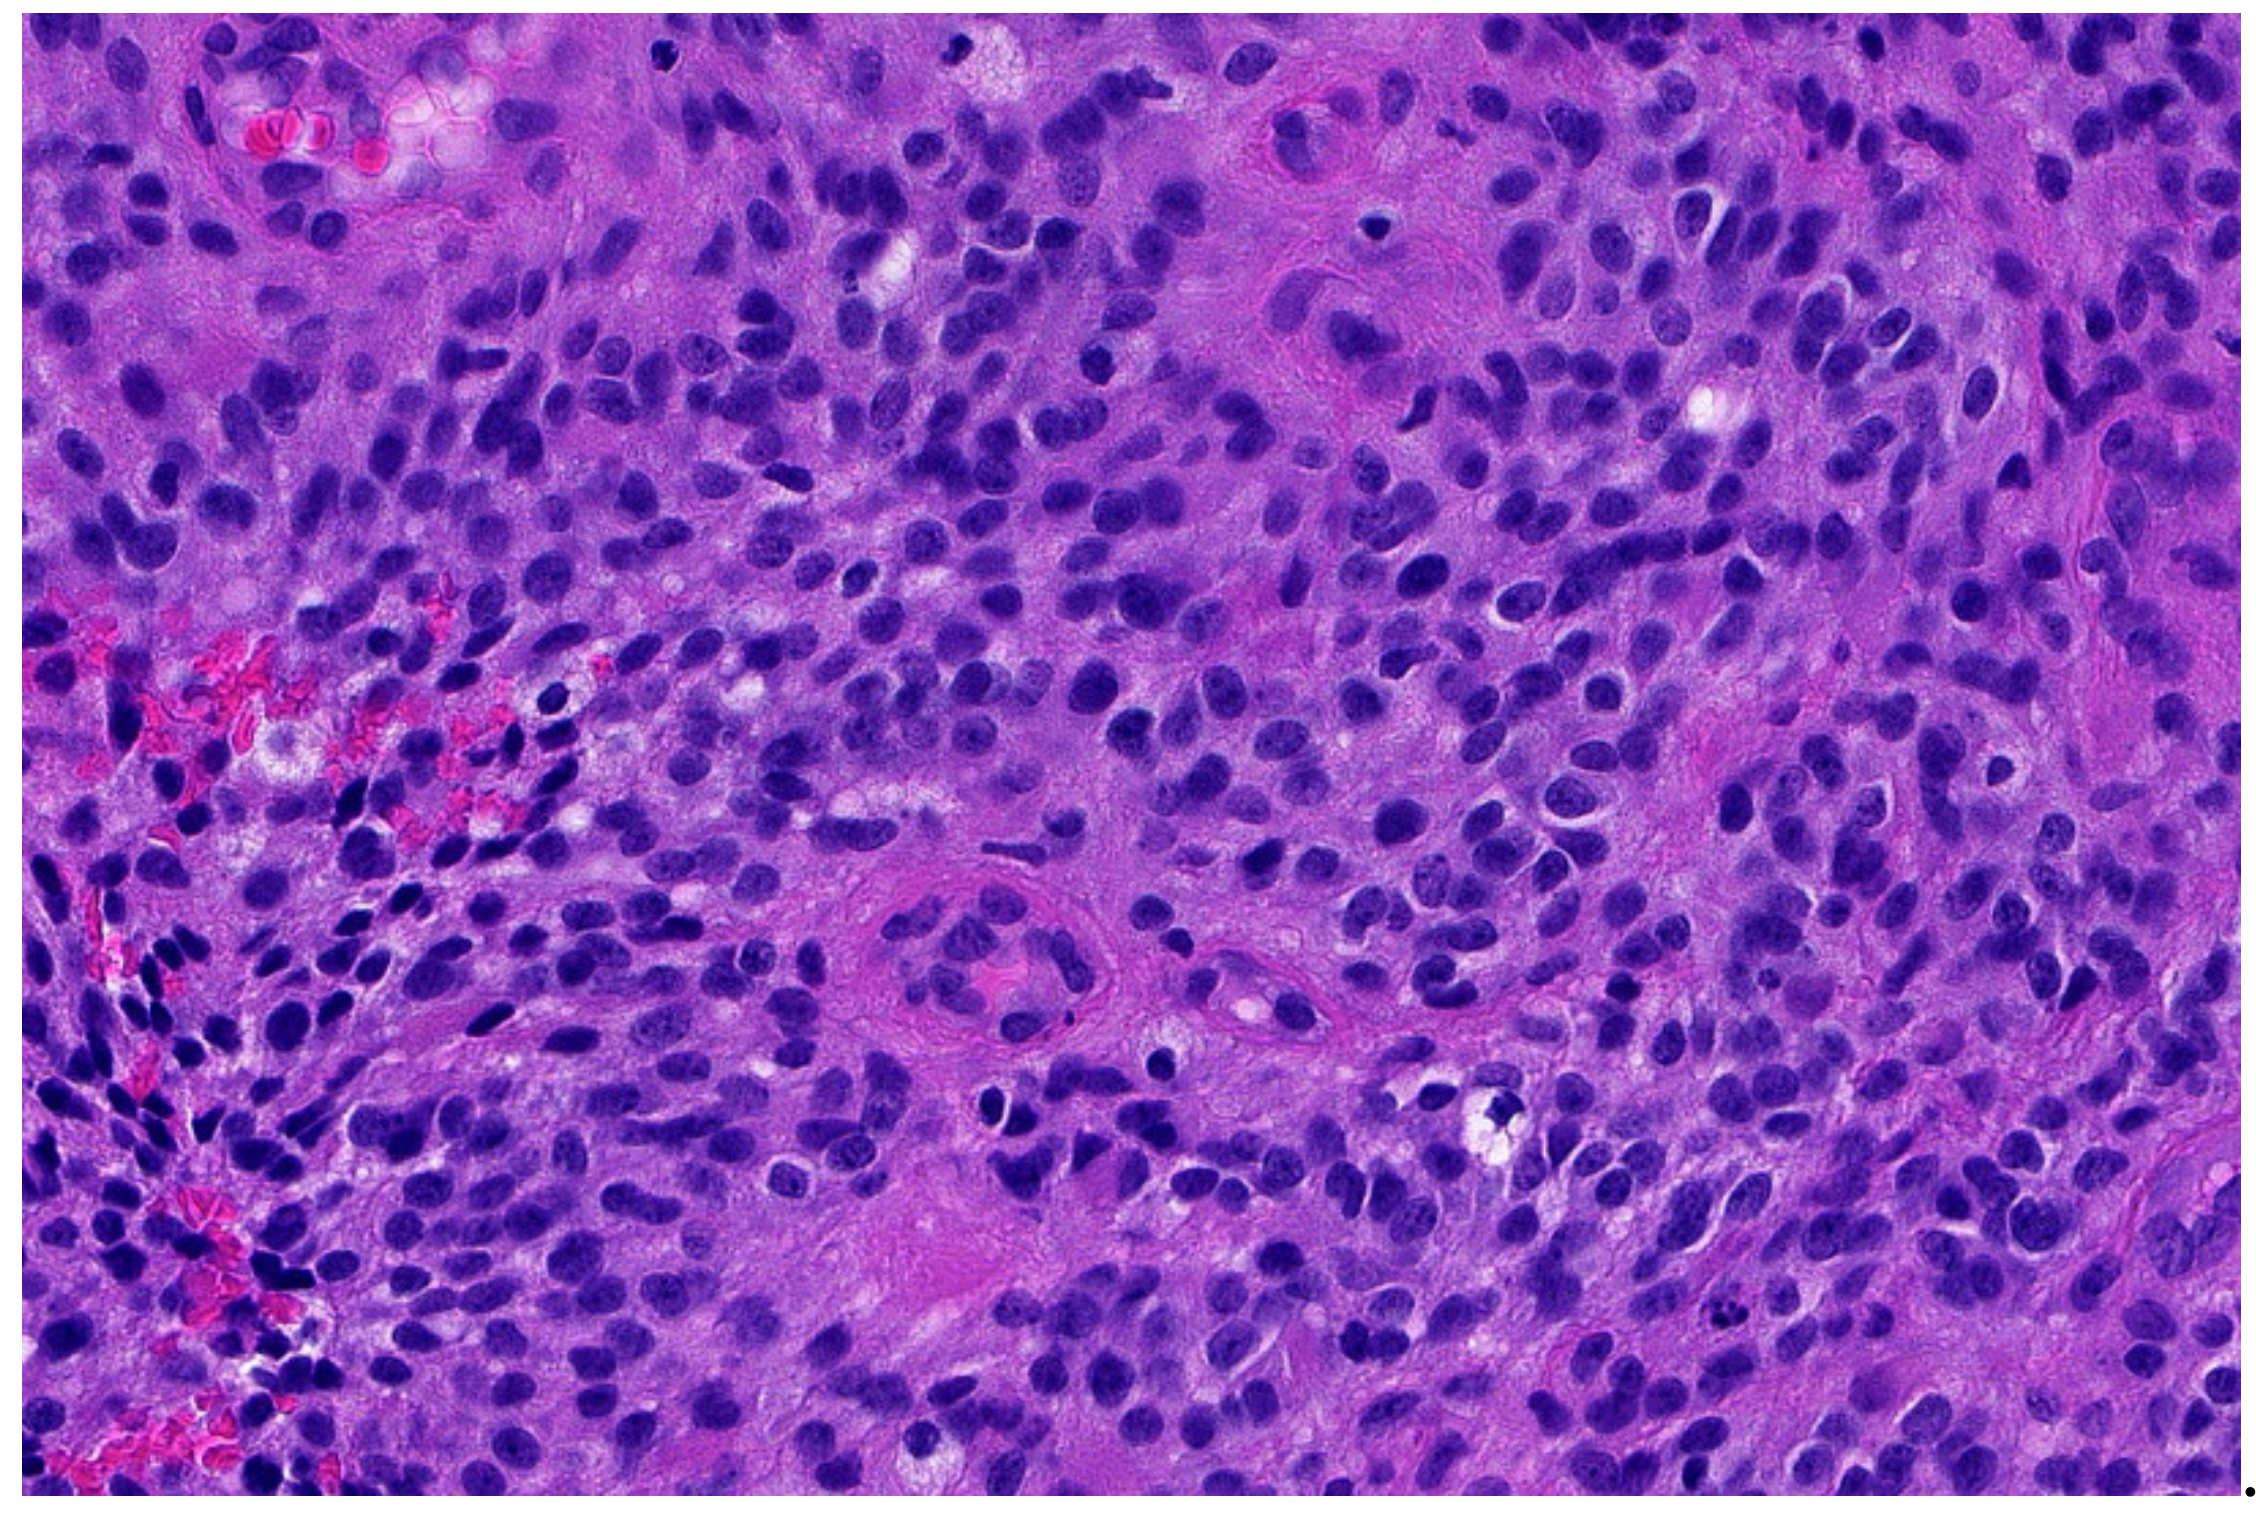

2. Ewing Sarcoma